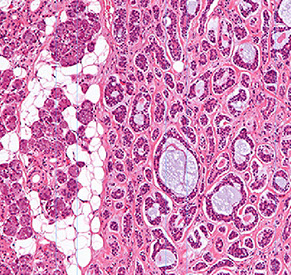

Acinic Cell Carcinoma

Malignant neoplasm with cells resembling normal serous acinar cells;

Parotids(4/5) > Submandibular > Minor salivary glands, F>M

May be bilateral or multicentric (like Warthin’s)

Tumors are generally small discrete lesions

- there is no b9 counterpart (acinic cell adenoma)

- grossly firm, circumscribed most of the time

Variable architecture (types) and cell morphology

Clear cytoplasm generally, but can be solid or vacuolated

- if cytoplasmic vacuoles present, may stain PAS (+); however they are just secretory granules and not mucin (as in MEC)

- usualy basophilic c lots of lymphoid infiltrate

- can look a little like thyroid

Can be in sheets or microcystic, glandular, follicular or papillary patterns

Usually few mitoses and little anaplasia

IHC: (+) PAS, PASD, (clear cells are PAS and mucin neg), keratin, amylase, transferrin, IgA, proline-rich protein, ANO1 (anoctamin-1)/DOG1 (Discovered On GIST-1), SOX10

- Negative GCDFP-15, MUC1, BRST-2 and mammaglobin and HER2

Clinical course dependent of degree of pleomorphism, though not well established

10-15% with LN mets, up to 35% recurrence

Both associated with worse prognosis

- otherwise fairly good 5-year survival (low-risk)